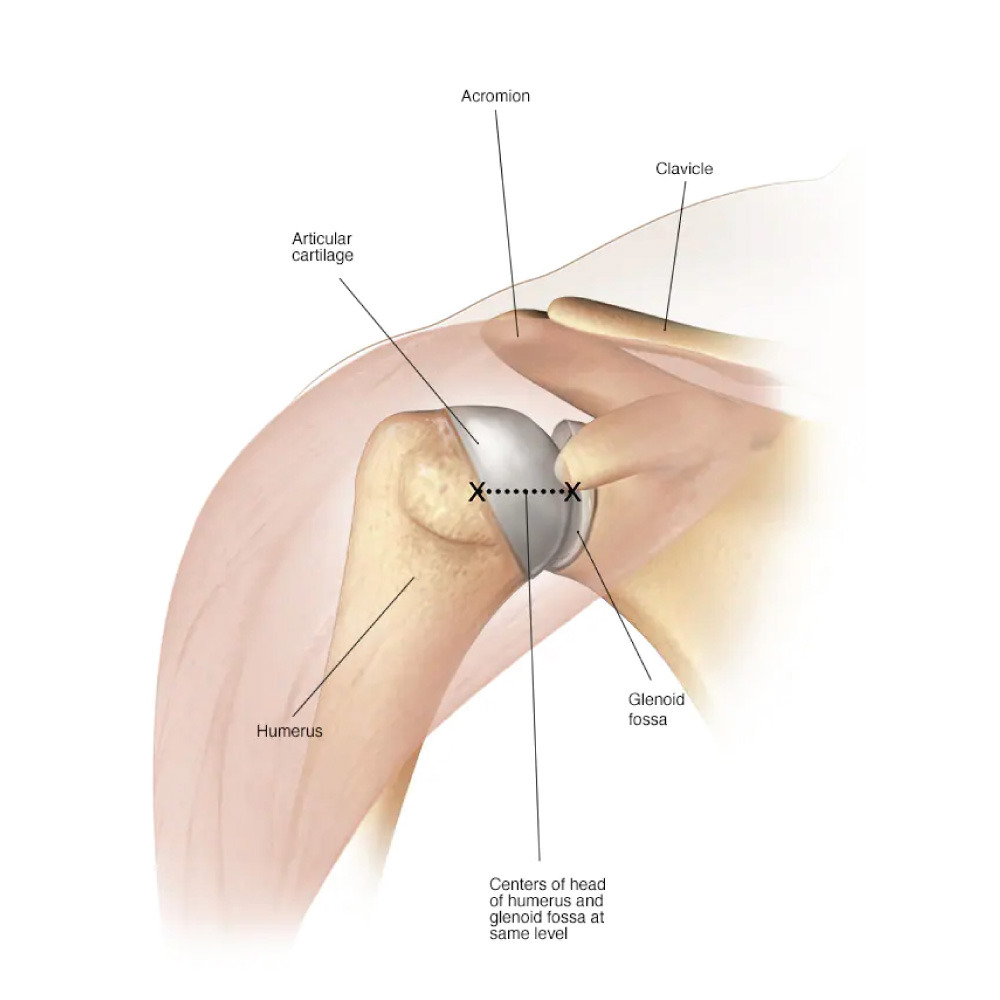

In shoulder replacement surgery, the damaged parts of the shoulder joint are removed and replaced with artificial components called implants. These implants are made of metal and medical-grade plastic and are designed to move like a natural shoulder joint. The main goal of this surgery is to reduce pain, improve mobility, and help patients return to an active, comfortable life.

Total Shoulder Replacement: Both the ball and socket of the shoulder joint are replaced.

Partial Shoulder Replacement: Only the damaged part of the joint is replaced.

Reverse Shoulder Replacement: Used when shoulder muscles are weak or damaged, especially the rotator cuff.